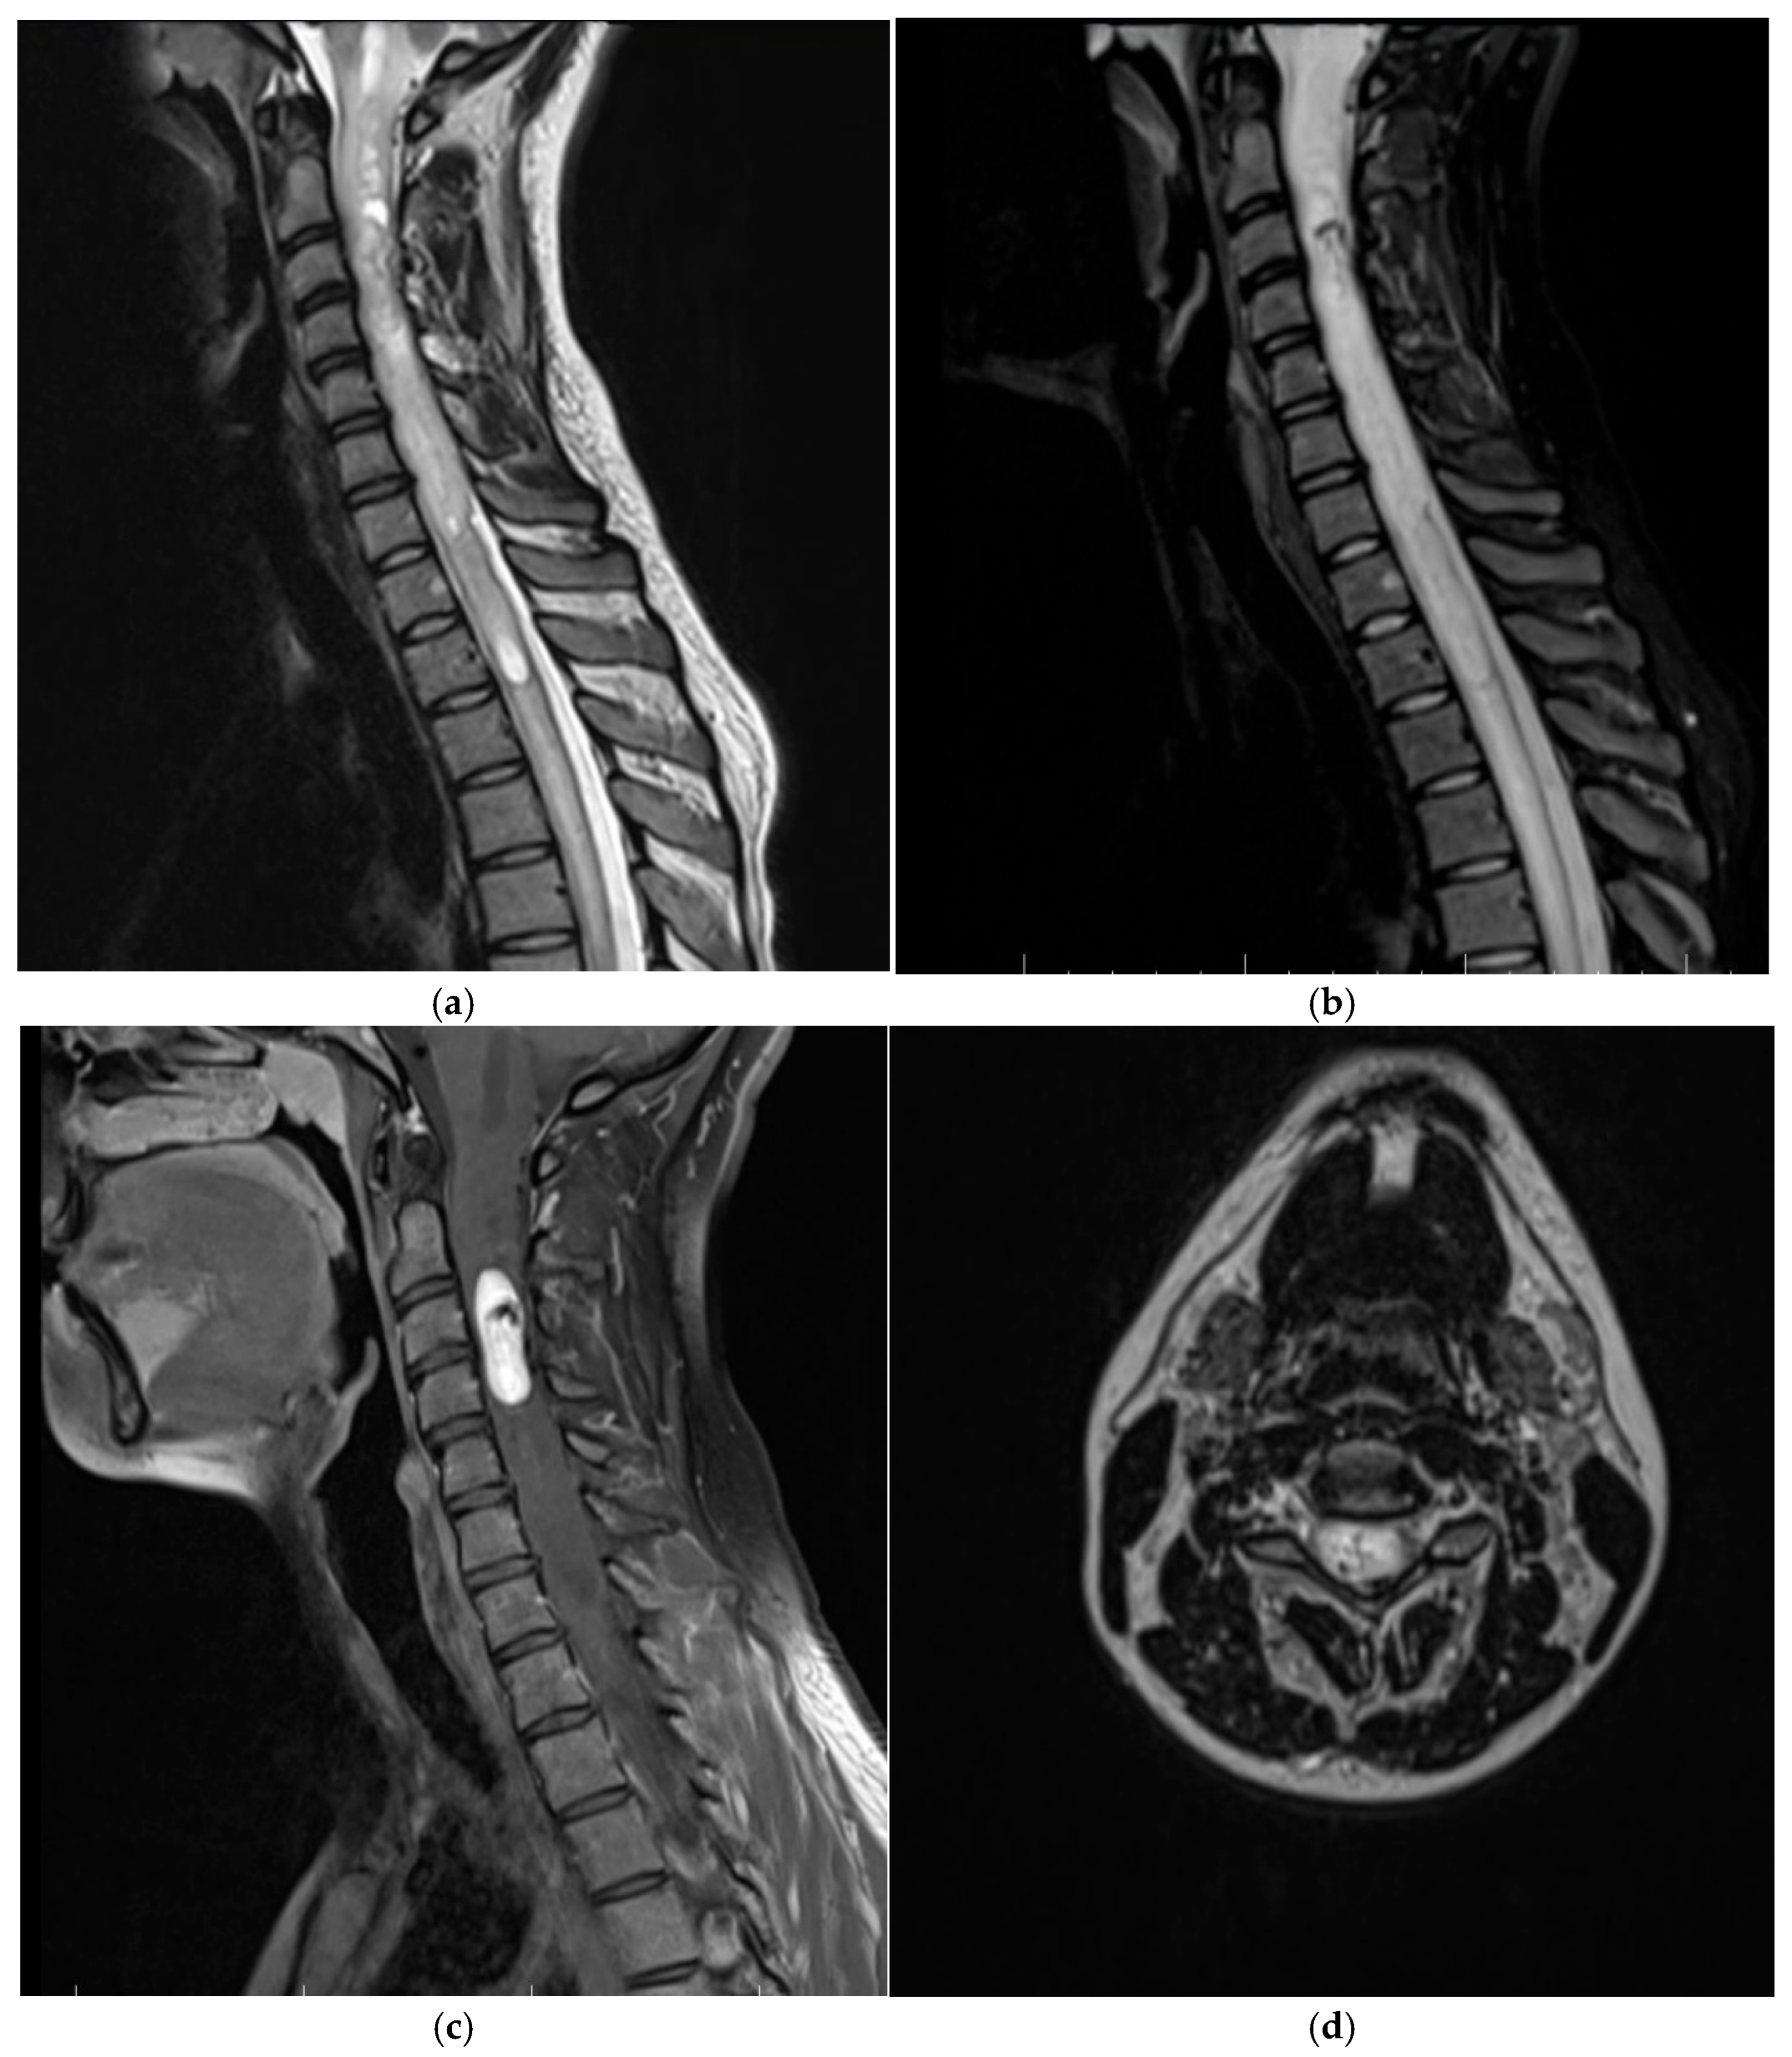

3.1.2. Patient Two